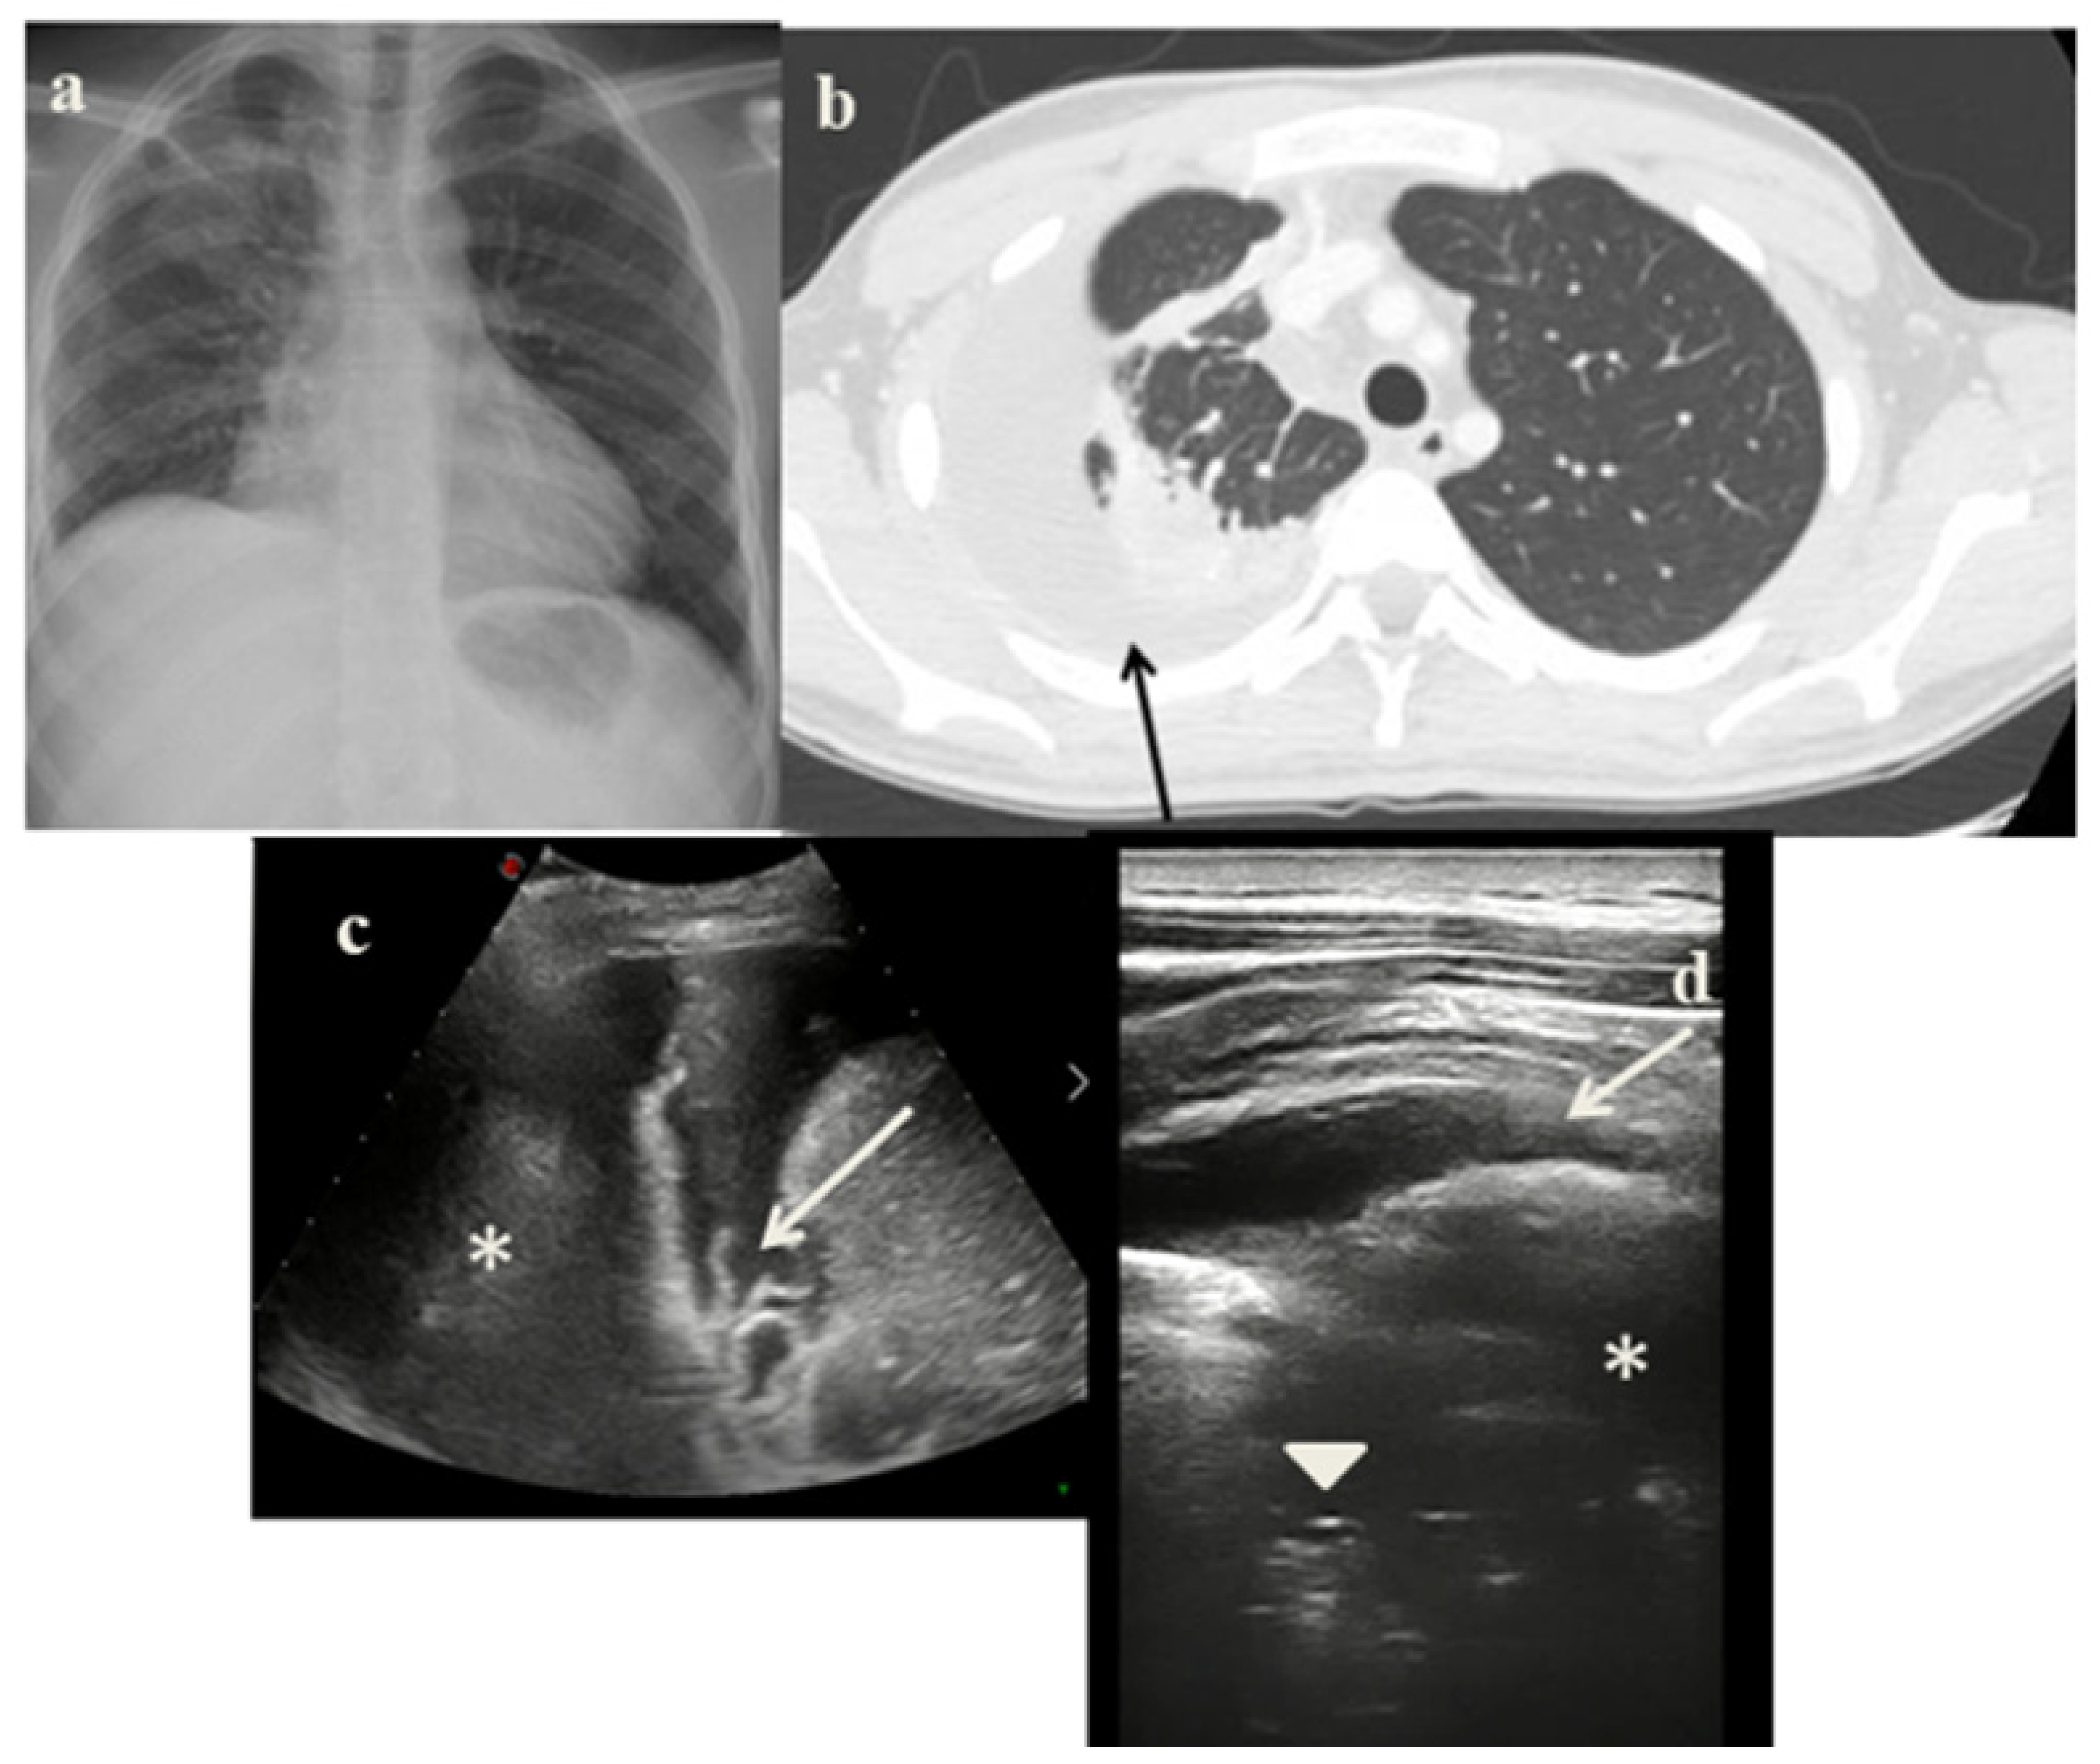

2.4. Case 4

- In the cases 2 and 4, it demonstrated its superiority compared to CXR in characterizing the pleural effusion and consolidation of an atelectatic nature (Figure 2c and Figure 4c); LUS is therefore useful as a non-invasive diagnostic instrumental support to identify and characterize a picture of tuberculous pleuritis.